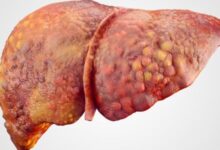

تعني دهون الكبد بأنّ هناك زيادةً في كمية الدهون المتراكمة في تجاويف الكبد ممّا يٌعيق عملها ويبطئه، الأمر الذي يؤشر إلى حالةٍ مرضيةٍ خطيرةٍ على صحة الإنسان تبدأ بتليّف الكبد وتنتهي بتشمّع الكبد، وقد يتطور المرض إلى التسبب بإصابة الكبد بالسرطان، كما تتسبب هذه الدهون بارتفاعٍ في نسبة الأنزيمات التي يفرزها الكبد مما ينتج عنها ارتفاع في مستوى الحديد في الدم.

تختلف مضاعفات تراكم الدهون في الكبد من شخصٍ إلى آخر؛ فالبعض تنتج لديه التهاباتٌ في الكبد تؤدي إلى توّقف عمل الكبد بالتدريج حتى تفقد قدرتها على العمل، فيفقد الجسم عضواً مهماً فيه، والبعض الآخر ينتج عنده تشمّعٌ وتليّفٌ في الكبد يتوقف عمله أيضاً، مما يتسبب بالوفاة.